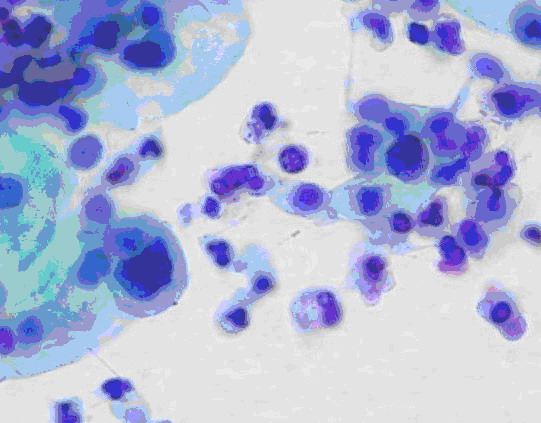

举例来说,慢性宫颈炎(宫颈糜烂)与宫颈癌在妇科阴道镜检查时观察到的表现可以相似。行宫颈刮片的细胞检查时看到的也可以相似(图1、2)。最后采取组织行病理切片检查,也是有相似之处,不是容易做出100%鉴别的(图3、4)。这样看来,如果仅一次检查(或一家医院检查),就肯定是癌,而行手术切除,是不慎重的,错误率是高的。最好是如果要手术切除,应到第二家医院或第二个医生核实后进行下一步治疗。

图1 宫颈炎看到的细胞

图2 宫颈癌看到的细胞